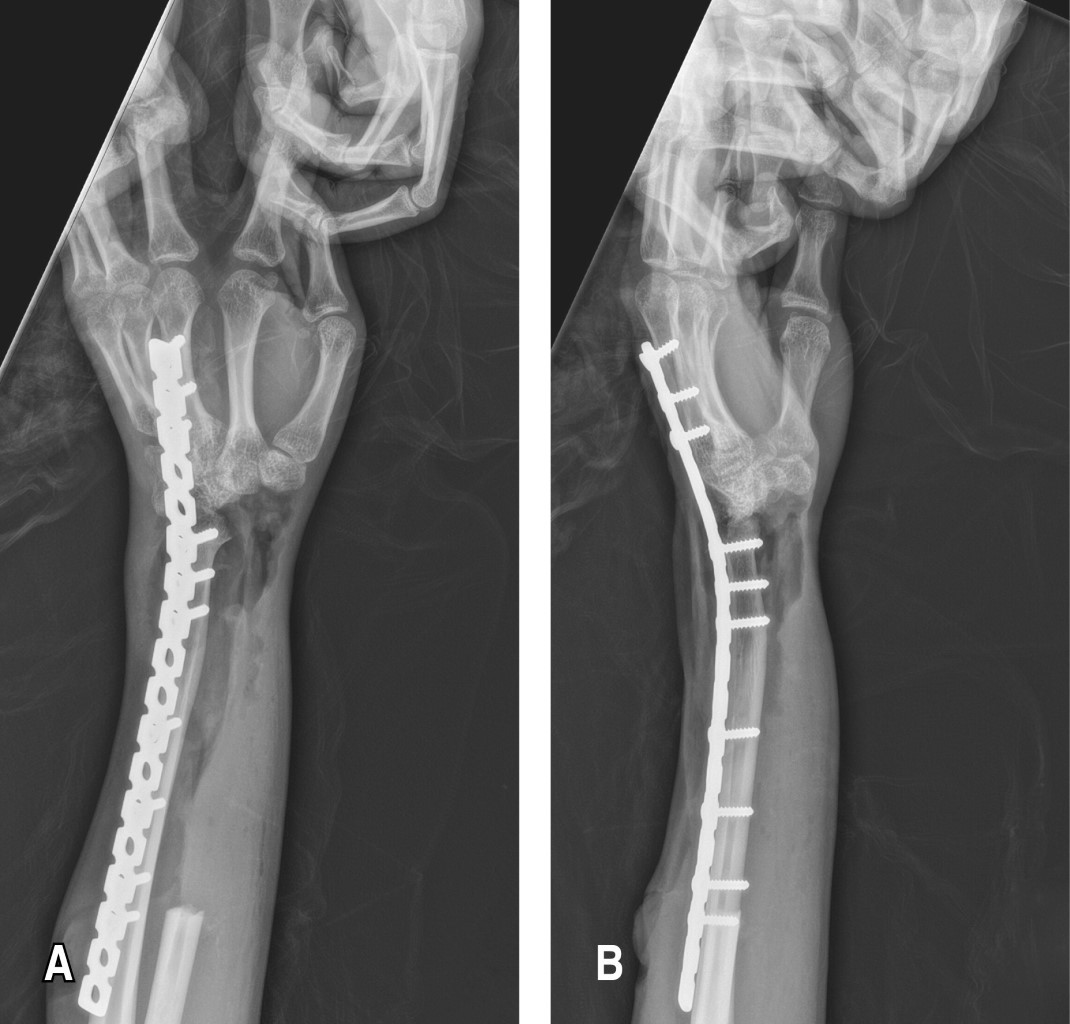

Posteriormente, es referido a la consulta de ortopedia en mayo de 2021 por presentar aumento de volumen a nivel del antebrazo, de crecimiento exponencial, presentando limitación a la pronosupinación, no a la flexoextensión, se solicitan radiografías anteroposterior y lateral de antebrazo, las cuales evidencian tumoración blástica, extracompartimental, excéntrica con reacción perióstica tipo triángulo de Codman de 11 × 5 × 4 cm (Figura 1). Se cita al paciente dos semanas después, con protocolo quirúrgico establecido se solicitan nuevas radiografías, encontrando aumento exponencial en tumoración, clínicamente dolor tumefacción, limitación de arcos de movilidad (Figura 2). Junio 2021. Se realiza biopsia escisional, mediante resección ampliada de radio derecho dejando márgenes de seguridad de aproximadamente 3 cm (Figura 3), exéresis de ganglio centinela y primera fila del carpo, centralización a tercer rayo de ulna y artrodesis con placa de reconstrucción de 18 orificios (Figura 4).

Como hallazgos postquirúrgicos se reporta tumoración de 15 × 8 cm neovascularizada con compromiso radial, de flexor palmar largo. En julio de 2021 el reporte de histopatología muestra resultado de osteosarcoma convencional de alto grado, osteoblástico en 65% y condroblástico en 35%, clínicamente con movilidad activa de extremidad, flexión y extensión de codo completa, prensión de mano fuerza 4 de 5 Daniels (Figura 5).